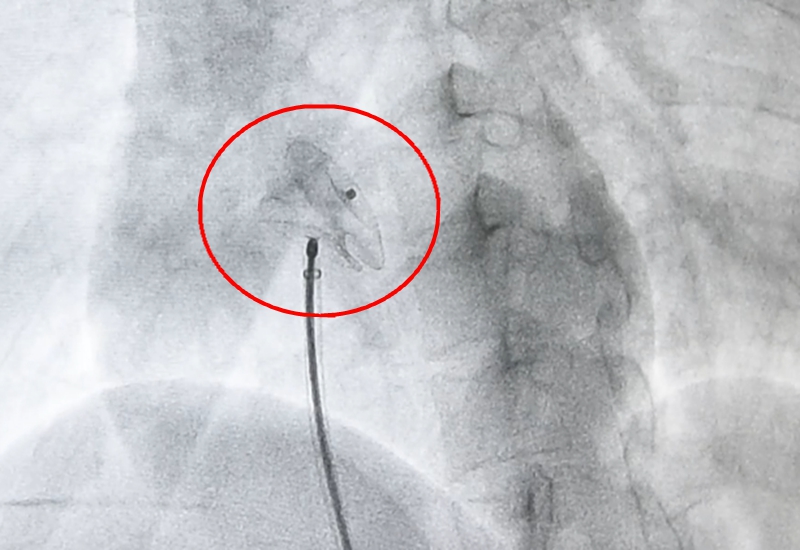

手术前,通过经食道心脏超声检查,明确小英心脏房间隔缺损为9*12毫米大小的椭圆形缺口。救心团队选用直径16毫米的封堵器作为补心工具。

从下肢静脉入口,救心团队利用一根携带封堵器的导丝,循着静脉一路探查,深入心脏内部,抵达缺损部位后,快速释放封堵器。

封堵器犹如一把“工”字型的雨伞,紧紧地卡在房间隔缺损处。术后即刻心超提示,房间隔缺损被完全封堵,左右心房血液分流最终消失!术后第二天,小英便顺利出院。